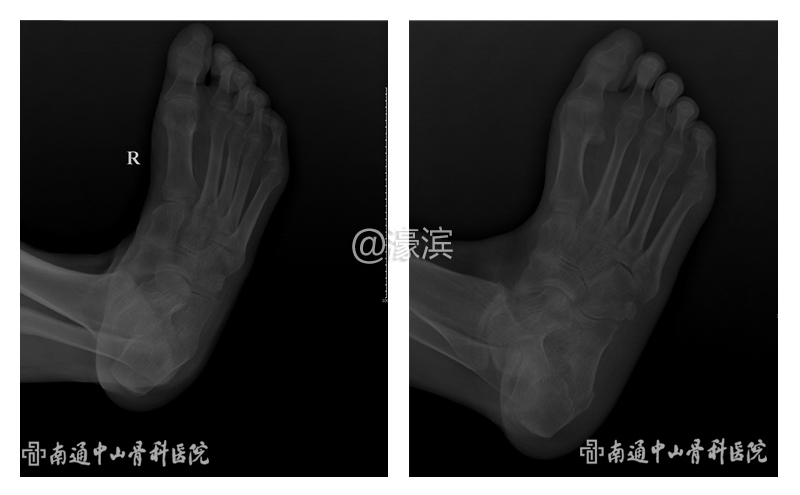

【案例】右足内翻要求截肢,中山骨科刀下留情为患者矫形成功 |